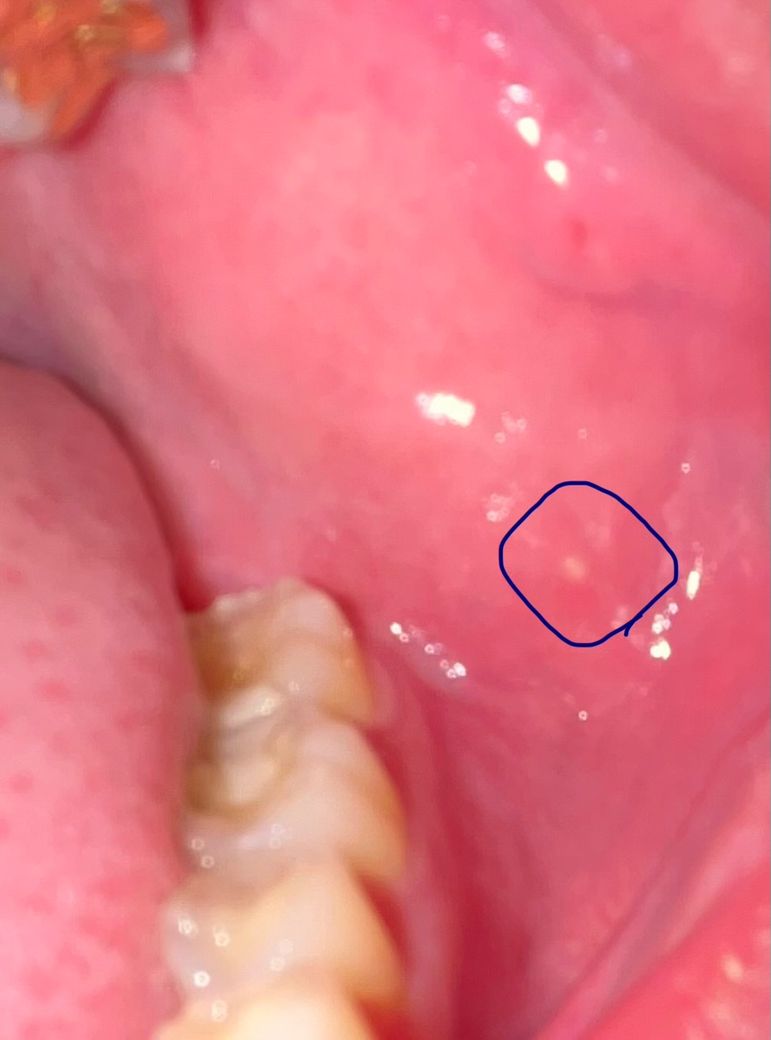

볼 안쪽 흰 좁쌀같은 뾰루지? 생겼습니다

얼마전에 잇몸이랑 볼살이 좀 붓고 뜨거워서 살펴보니까

흰 좁쌀같음 뾰루지? 점액종? 같은데 생겼는데 이게 뭘까요 눌러도 아프지 않고 고름 같은게 나오지도 않더라구요

뾰루지처럼 살짝 튀어나와 있기만 힙니다. 지금은 잇몸 살짝 욱신거리고 붓기는 가라앉았습니다.

생긴지 4일정도 된것 같습니다.

점액종일 가능성은 극히 적어보이며 단순한 지방종일 가능성이 더 커 보입니다. 하지만 구강내에 나타난 연조직 질환은 조직검사를 하지 않고서는 정확한 진단을 하기에 어려움이 있습니다. 지금 나타난 부위가 해당 병소에 의해서 불편감이 갑자기 나타나거나 환부가 커지거나 하면 바로 치과를 방문하여 검사를 해보시길 바랍니다.

해당 부위와 증상은 별개로 생각하셔야할거 같으며 볼부분에 있는 것은 피지선 과립으로 보입니다. 사진이 흐려 정확하지는 않으나 성상 변화 및 크기 변화가 없다면 경과관찰 하시고 이상있을 시 즉시 병원 내원하시기를 바랍니다.